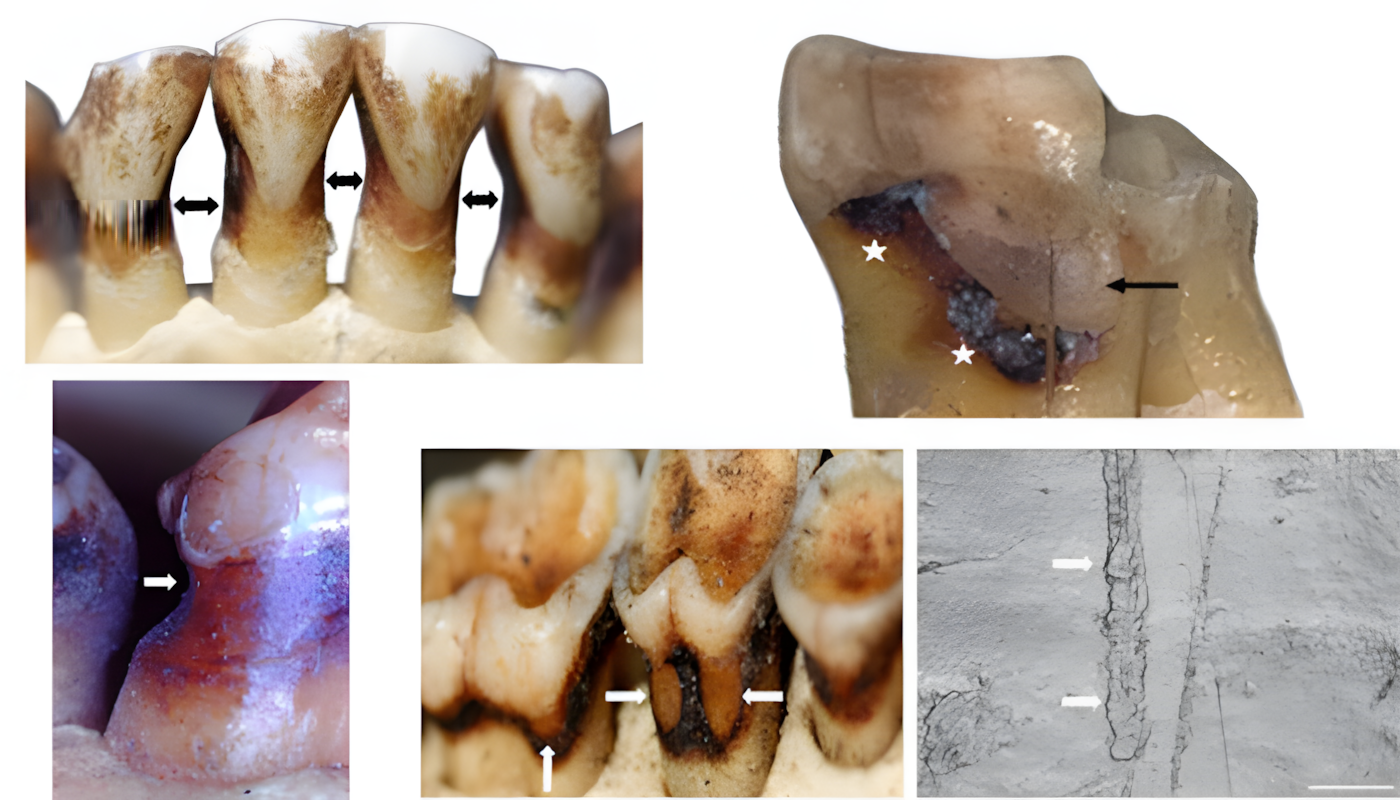

우리는 비우식성 치경부 병변non-carious cervical lesions (충치로 인한 것이 아닌 치아 경부 조직 손실을 지칭)을 조사했다.

현미경, 3D 스캔, 조직 손실 측정을 사용하여 아주 작은 병변까지도 기록했다.

약 4% 개체에서 병변이 발견되었다.

일부는 화석 인류의 고전적인 "이쑤시개 홈"과 거의 동일하게 보였으며, 미세한 평행 긁힘과 끝이 뾰족한 모양을 갖추고 있었다.

다른 병변들은 특히 앞니에서 얕고 매끄러웠는데, 이는 많은 영장류가 다량으로 섭취하는 산성 과일 때문일 가능성이 높다.

우리는 굴절 손상abfraction을 전혀 발견하지 못했다.

극도로 질긴 식습관과 강력한 저작력chewing forces을 가진 종들을 연구했지만 현대 치과에서 흔히 볼 수 있는 쐐기 모양 결함을 보인 영장류는 단 한 마리도 없었다.